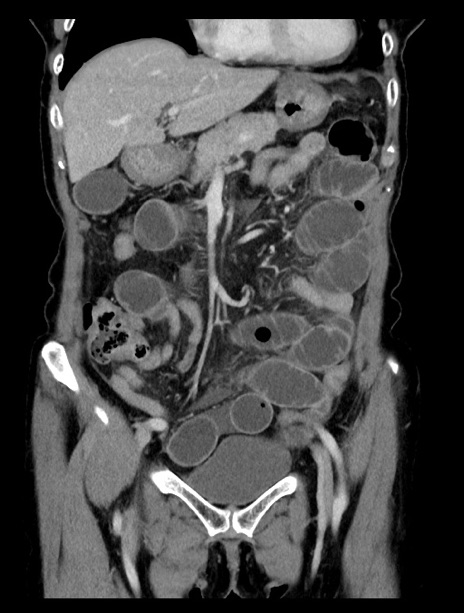

症例23(冠状断像)

【症例】70歳代女性

【主訴】下腹部痛・嘔吐

【現病歴】2日前より腹痛あり。昨日嘔吐あり。症状改善しないため来院。

【既往歴】胃GISTに対して胃部分切除後。

【身体所見】BT 37.1℃、BP 128/77mmHg、腹部:平坦・軟、下腹部に圧痛あり。

【データ】WBC 10200、CRP 0.31